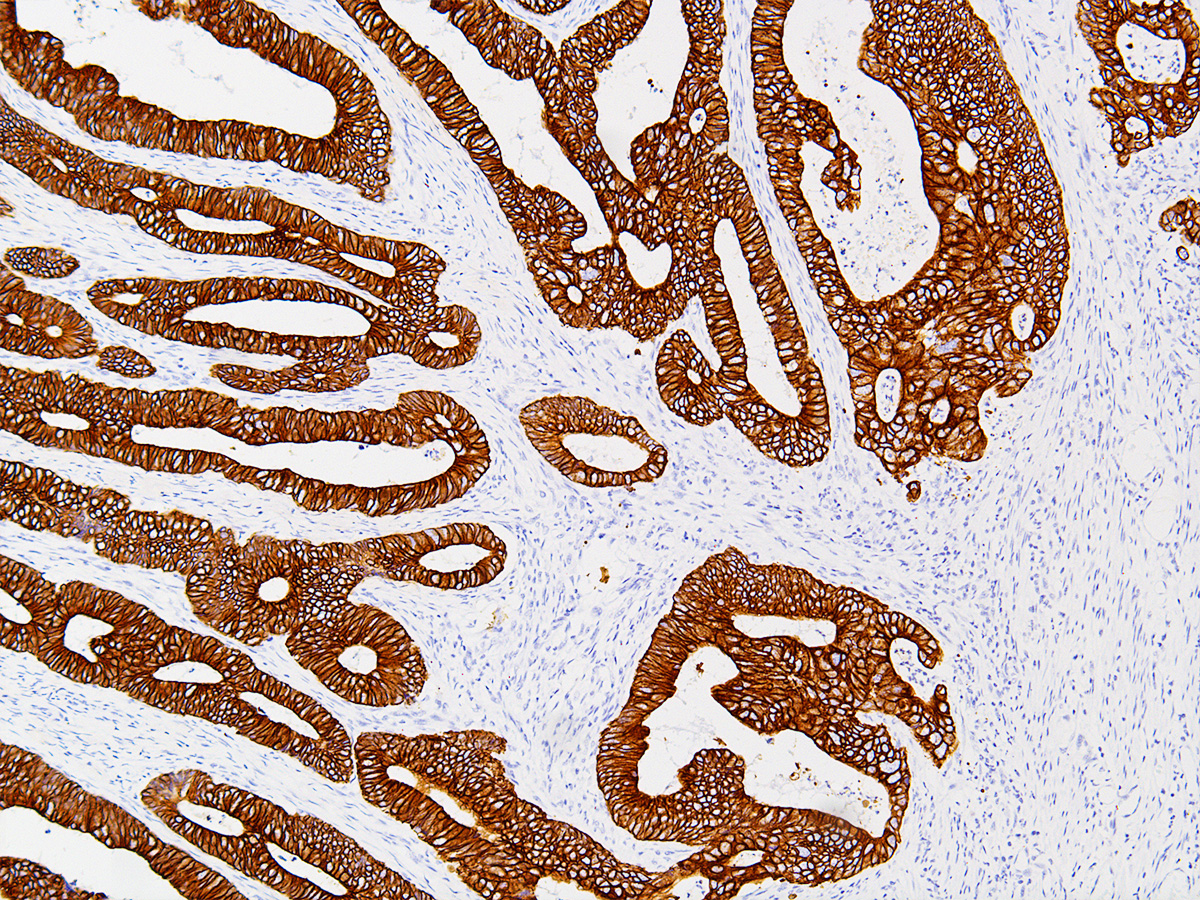

Cytokeratin 19 Antibody

应用详情:Recommended working dilution range:1:100 - 1:200

图片:

Cytokeratin 19 Antibody (P1008) on Colon- 10x

Cytokeratin 19 Antibody (P1008) on Colon- 20x

Cytokeratin 19 Antibody (P1008) on Colon- 40x